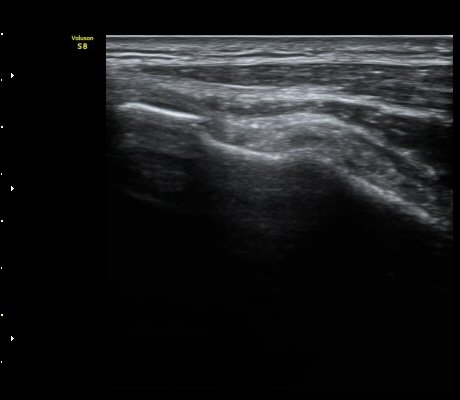

ÆÈ²ÞÄ¡ µÚÂÊ °üÀý¸éÀ¸·ÎºÎÅÍ 2.5cm ¾Æ·¡¿¡¼­ ¿ä°ñ°ü°ú ô°ñ °æ°èºÎ¸¦ Ⱦ´Ü¸éÀ¸·Î

°Ë»çÇÏ´Ï ¿ä°ñµÎ¿¡ ºÎÂøµÈ À̵ιڱ٠ÈûÁÙÀÌ °üÂûµÈ´Ù(±×¸² 9). Á¾´Ü¸é°Ë»ç¿¡¼­µµ

À̵ιڱ٠ÈûÁÙ°ú ¿ä°ñµÎ°¡ ¶Ñ·ÈÈ÷ °üÂûµÈ´Ù(±×¸² 10).